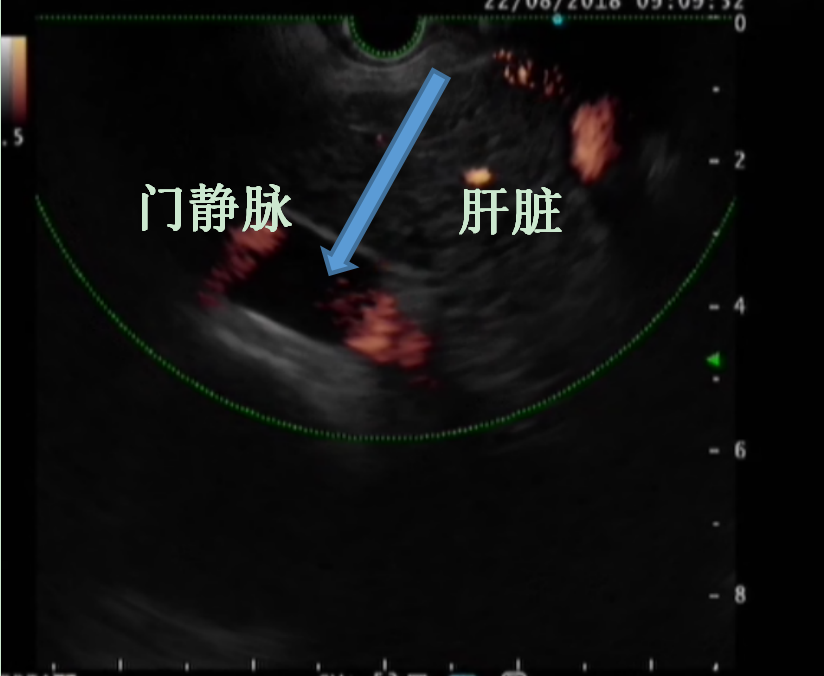

骨髓移植示意图

患者是一名50岁中年男性,湖南益阳人,乙肝病史20余年,近年来逐渐出现乙肝肝硬化失代偿期症状:肝功能明显减退、脾功能亢进、大量腹水,多次呕血、黑便,近年来需频繁出入医院。王芬教授在查房时向患者表示可应用“自体骨髓细胞”治疗肝硬化,骨髓中的间充质干细胞可促进促进肝小叶重塑,骨髓造血干细胞在肝脏内可定向分化成新的肝细胞,骨髓自带的细胞因子也可以刺激肝脏原始祖细胞产生新的肝细胞,使产白蛋白的肝细胞数量迅速增加,有望改善患者肝功能、消除腹水、延缓肝硬化进展。在评估患者病情、详细沟通手术相关事项并签署知情同意书后,入院第4天,王芬教授及其团队从患者体内抽出30ml全骨髓,通过超声内镜途径,顺利经门静脉精准定植到肝脏内,术中患者生命体征平稳,未出现明显不适。术后半月随访患者发现,其白蛋白指标由28.9g/L上升到37.8g/L,一月后腹水完全消退。